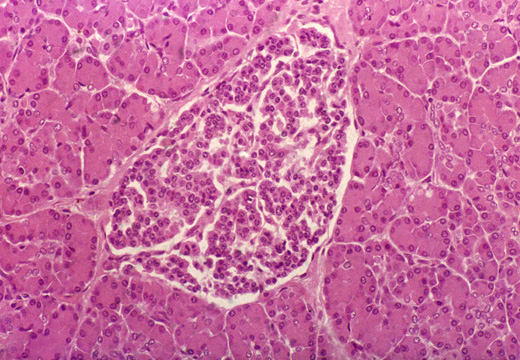

病理中心

擁有實力強勁的研發團隊,秉承“ 做中國人自己病理產品” 的理念,堅持從細節做起,勇于創新。業務涵蓋病理診斷中組織脫水、切片、染色和細胞制片等關鍵流程,主要產品包括達科為全自動智能染色機DP260系列、達科為全封閉智能組織脫水機HP300系列、達優染色液系列、德國PFM輪轉式石蠟切片機系列、韓國佰達因液基制片機Cellprep系列、龍首輪轉式石蠟切片機、冷凍切片機系列等。其中自主研發的全自動智能染色機和全封閉智能組織脫水機不僅在國有品牌中引領先進技術,與進口品牌相比也毫不遜色,其獨特的軟件功能與持久穩定的性能在臨床中大放異彩,一舉打破國有品牌在病理行業中的低端形象,同時也受到了來自美國、德國、法國、匈牙利、香港等國際病理專家的好評,以及歐美代理商的積極反應。